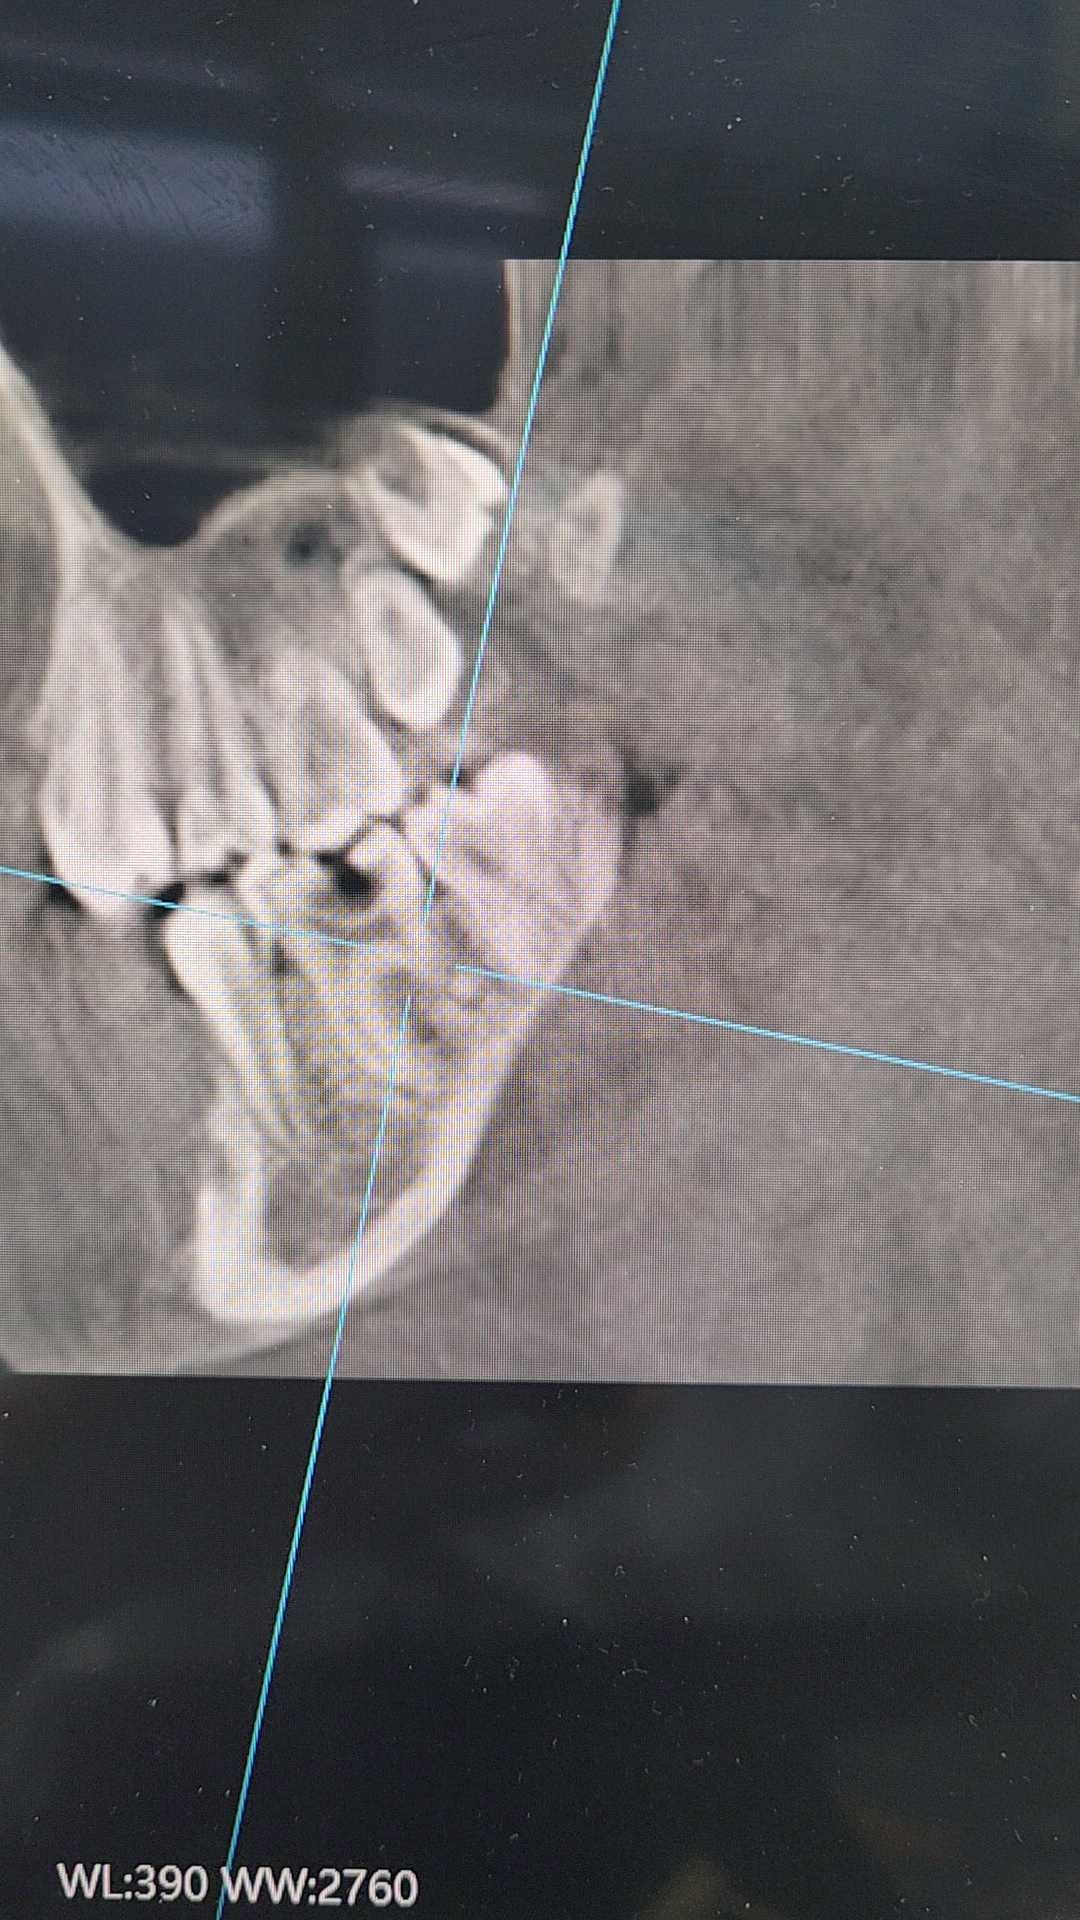

患者12岁,女,主诉右下后牙不适疼痛2周余伴夜间疼。查体见:#46颌面深龋,色黑,质软,冷刺激反应迟钝,叩++,松动度无。

口腔全景片示:#46颌面低密度龋坏影像及髓,远中根中1/2可见疑似高密度根折影像,根尖未见明显异常。

CBCT协诊。

患者否认咬硬物史。

想请教各位同仁们像根折吗?